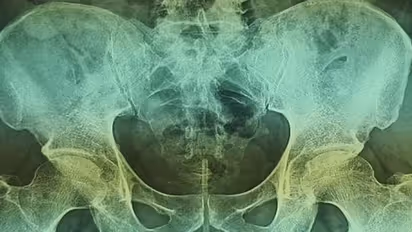

ഡോക്ടര്മാര് നടത്തിയ പ്രാഥമിക പരിശോധനയില് തന്നെ ഒരു കാര്യം വ്യക്തമായി. അയാളുടെ ലിംഗത്തിനുള്ളില് എന്തോ ഒരു വസ്തു കിടക്കുന്നുണ്ട്. തുടര്ന്ന് എക്സ് റേ പരിശോധന നടത്തിയപ്പോള് അവര് കണ്ടത് ഞെട്ടിക്കുന്നൊരു കാര്യമായിരുന്നു.

ലിംഗത്തിനുള്ളില് ഒരു കഷണം ഇലക്ട്രിക്കല് വയര്!

അത് മൂത്രനാളിയിലേക്ക് തുളഞ്ഞുകയറിയിരുന്നു. മാത്രമല്ല, അത് മൂത്രമൊഴിക്കുന്ന ദ്വാരത്തോട് തൊട്ടുകിടക്കുകയായിരുന്നു.

64-വയസ്സുള്ള പാക്കിസ്താന്കാരന്റെ ലിംഗത്തിനുള്ളില് നിന്നാണ് 18 സെന്റി മീറ്റര് നീളമുള്ള ഈ വയര് കണ്ടെത്തിയത്. മൂത്രമൊഴിക്കുന്നതിന് തടസ്സം നേരിട്ടപ്പോള്, ആരോ പറഞ്ഞതുപ്രകാരമാണ് ഇയാള് വയര് അകത്തേക്ക് തള്ളിക്കയറ്റിയത്. തുടര്ന്ന് ഇത് അകത്ത് കുടുങ്ങിക്കിടന്നു. മൂത്രനാളിയിലേക്ക് ഇത് ചെന്നതോടെ മൂത്രമാഴിക്കുന്നതിന് ബുദ്ധിമുട്ടുണ്ടായി. ഒരാഴ്ചയിലേറെ ബുദ്ധിമുട്ട് സഹിച്ച ഇയാള് ആദ്യം ഹോസ്പിറ്റലില് പോവാന് മടികാണിച്ചു. പിന്നീട്, നിവൃത്തിയില്ലാതെയാണ് കറാച്ചി അബ്ബാസി ഷഹീദ് ഹോസ്പിറ്റലില് എത്തിയത്.